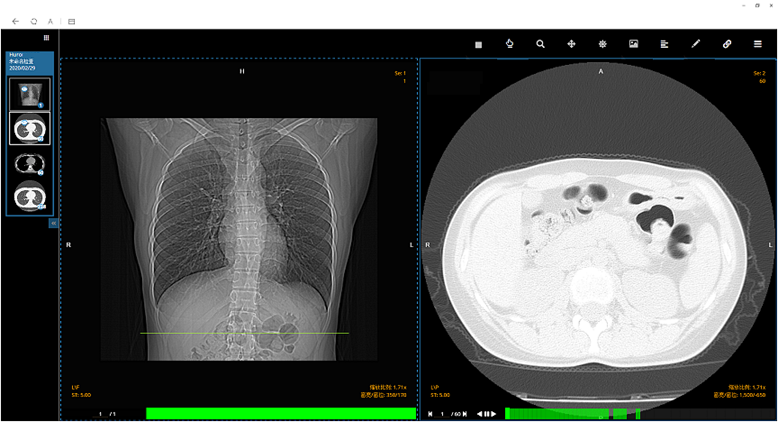

(阅片)